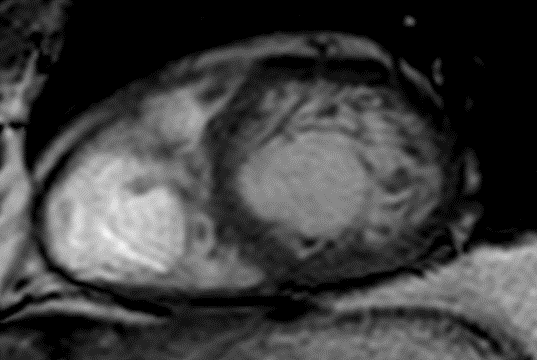

MRI scan

Example showing increased trabecular muscle.